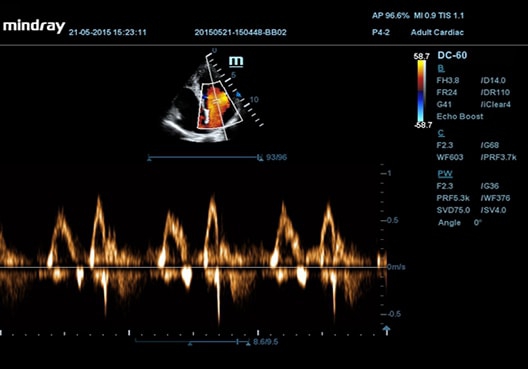

Mindray DC-55 обладает особым преимуществом - независимо от физической конституции пациента и плотности тканей, он обеспечивает высокое качество изображений без нежелательной зернистости. Это достигается благодаря использованию специальной технологии формирования мульти-луча и режима тканевого доплера с количественным анализом.

• Режимы сканирования B/M/Цветовой доплер CDI/Цветной M/Энергетический доплер

• Импульсно-волновой доплер (включая режим высокой частоты повторения импульсов HPRF)

• Echo Boost™ - режим улучшенной визуализации для кардиологии